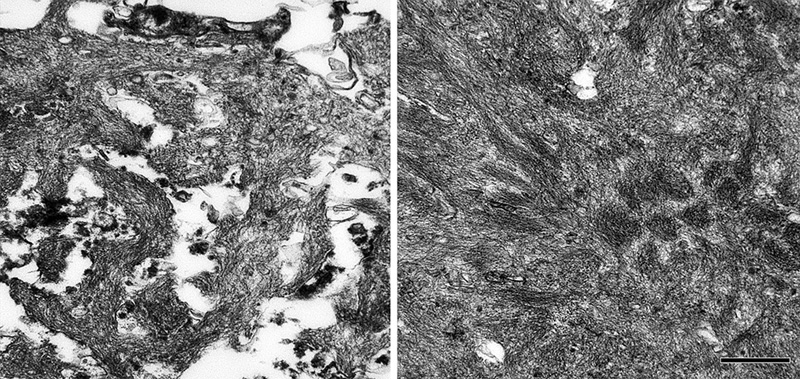

Certain types of Aβ plaque are typical of the brain compartments in which they develop, e.g., in the cerebellum, basal ganglia, or different cortical regions and laminae (see [139]). In the white matter, distinctive granular accumulations of Aβ [143] occur to varying degrees (Figure 11). These clusters consist of fibrillar Aβ lying outside of the axons, and they appear not to be associated with obvious tauopathy or other abnormalities of the axons themselves [143], although their functional significance is largely unexplored.

Figure 11. Aβ deposits in white matter of an AD patient comprise clusters of small puncta and filamentous bundles. Left: Light-micrograph of a cluster immunolabeled with antibody 4G8 (Nissl counterstain). Right, electron micrograph of a punctum immunolabeled with antibody 4G8 (black dots are gold particles bound to the secondary antibody). Bars = 20μm (left) and 200nm (right).